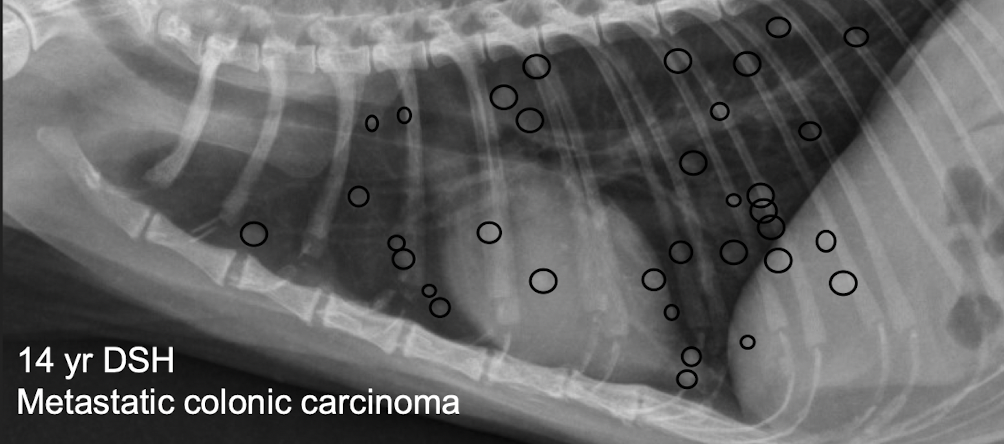

what kind of pattern

nodular intersitial pattern- can see > 3-5 mm nodules

• Metastatic pulmonary neoplasia

• Granulomatous disease →Heartworm, Fungal disease

Fluid-filled bullae, Cysts, Hematomas, Abscesses

(“CHANG” = Cyst, hematoma, abscess, neoplasia, granuloma)